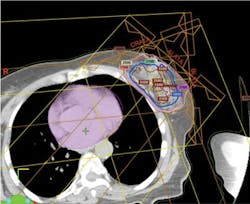

External-beam proton irradiation has a significant reduction in integral dose of radiation to the patient that is 60% lower than any external-beam photon (standard form of breast cancer irradiation therapy). The proton beam does not have an exit dose. It stops short at a pre-planned designated point just past the tumor bed (see Figure 2).

Radiologists, nuclear physicists, and dosimetricists create a computerized plan that controls the proton beam so that adjacent healthy tissue and organs are unaffected by the irradiation therapy. Planning of radiation distribution is part of both photon and proton treatment plans, but proton therapy can be delivered with great accuracy since proton beams can be controlled. The computerized plan is set to designate exactly where the beam starts and stops in relationship to the lumpectomy cavity.14,15